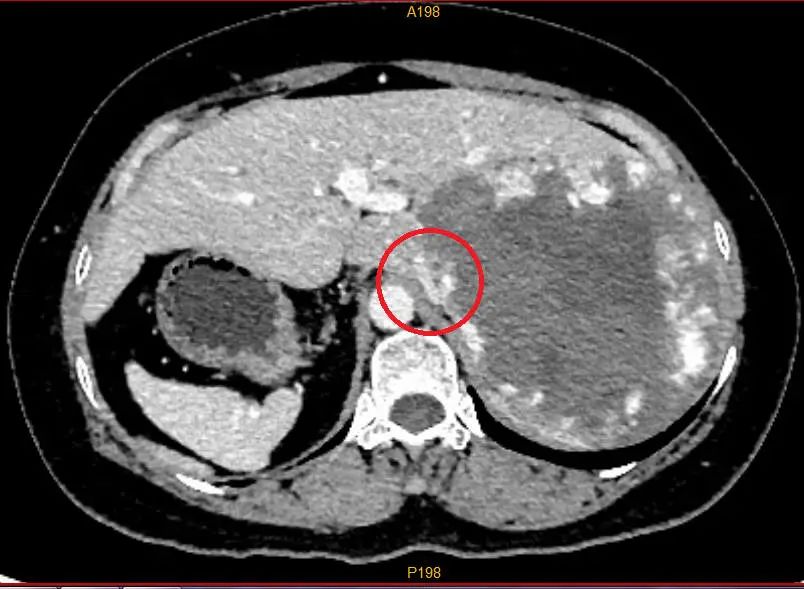

▲CT拍片可见卢女士腹腔脏器完全反位,胃及脾在右边,反位的右肝在左边,红圈处标记的下腔静脉已被巨大血管瘤压迫包绕,粘连浸润明显。图片来源:广西医科大学附属武鸣医院

据医生介绍,卢女士的血管瘤体积巨大,已经占据她整个右肝范围,必须进行手术。但是,血管瘤一旦在术中破裂,止血异常困难,手术可能危及生命。此外,卢女士反着长的器官极大增加了手术难度,属于国内外均罕见记载的疑难手术病例,手术困难重重,风险很大。

历时5个小时的手术后,医生从卢女士体内切除出一个15×14×12厘米的巨大血管瘤。目前,卢女士恢复良好,已顺利出院。